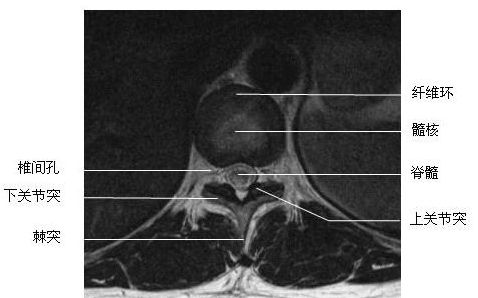

胸段横断面-MRI图

胸段横断面-MRI